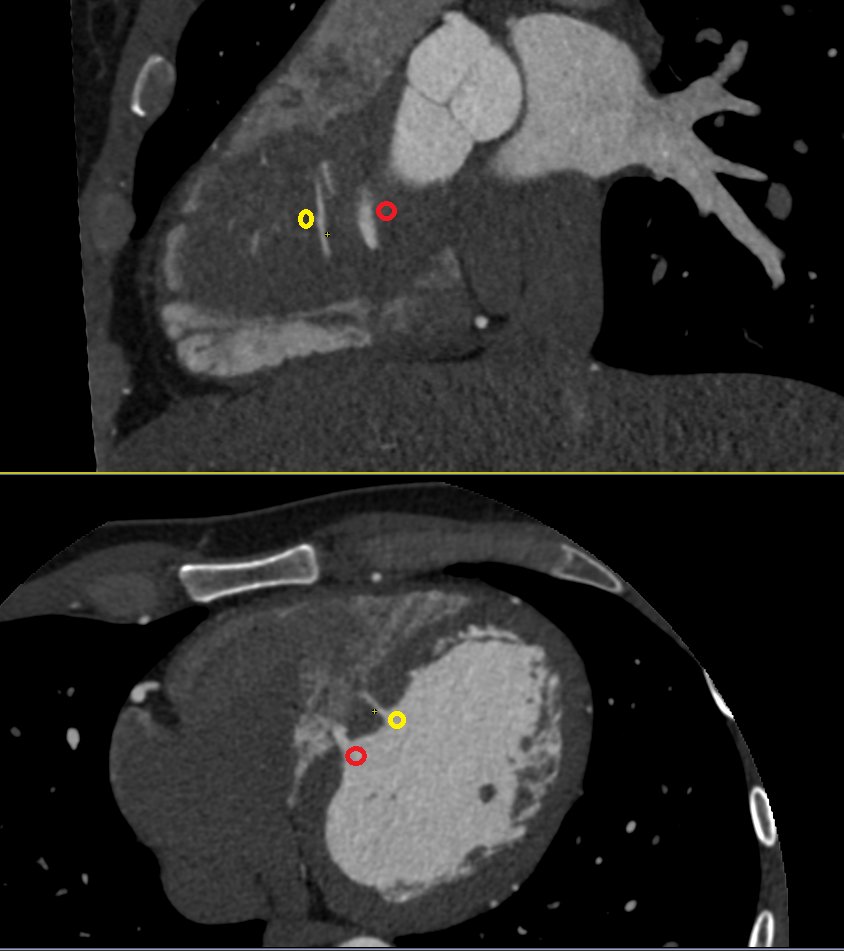

Nice example of a sort of Type IV LAD #YesCCT short LAD which becomes a septal branch with a branch off the prox RCA coursing anterior to the RVOT to the anterior interventricular groove @Heart_SCCT